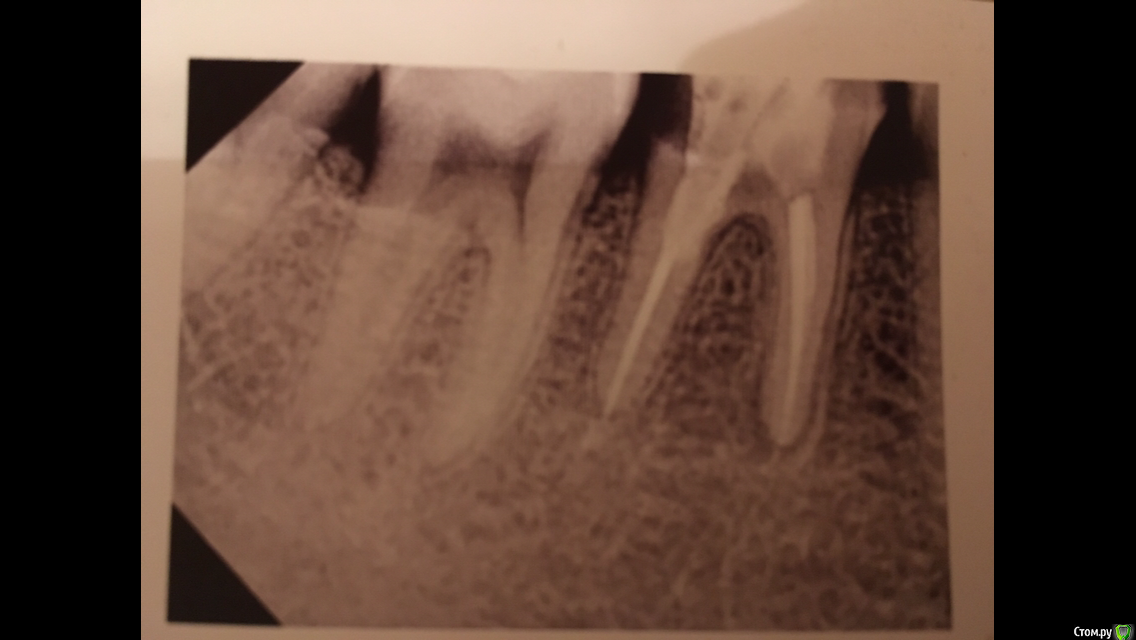

Fyodor333 Опубликовано 25 октября, 2018 Поделиться Опубликовано 25 октября, 2018 Обращаюсь за помощью. 2 дня назад поставили пломбу со стекловолоконным штифтом вместо разрушившейся старой. Третий день есть боли при надкусываи, пару раз за 2 дня при жевании острая боль. Сегодня боли полегче, но снимок все равно сделал, сказали вроде как нормально и отправили. На снимке видно очень много белой области, как будто расширила отверстие больше, чем нужно. Действительно ли все нормально, нету ли перфорации ? Прикрепляю снимки до и после установки новой пломбы. Ссылка на комментарий

Fyodor333 Опубликовано 30 октября, 2018 Автор Поделиться Опубликовано 30 октября, 2018 Обращаюсь за помощью. 2 дня назад поставили пломбу со стекловолоконным штифтом вместо разрушившейся старой. Третий день есть боли при надкусываи, пару раз за 2 дня при жевании острая боль. Сегодня боли полегче, но снимок все равно сделал, сказали вроде как нормально и отправили. На снимке видно очень много белой области, как будто расширила отверстие больше, чем нужно. Действительно ли все нормально, нету ли перфорации ? Прикрепляю снимки до и после установки новой пломбы. Ссылка на комментарий

Павел7809 Опубликовано 31 октября, 2018 Поделиться Опубликовано 31 октября, 2018 Идет 8-й день, боль не прошла, особенно во второй половине дня периодически ноет, отдает в челюсть(((похоже на то , что все таки там перфо.. Ссылка на комментарий

red_butler Опубликовано 1 ноября, 2018 Поделиться Опубликовано 1 ноября, 2018 Перфорации может и нет, но периодонтит есть а дистальной (дальней) стенки нет. Ссылка на комментарий

red_butler Опубликовано 8 ноября, 2018 Поделиться Опубликовано 8 ноября, 2018 А в какой части снимка виден периодонтит у верхушки медиального (правого) корня 5 лет я ходил с запломбированными каналами и зуб ни разу не беспокоил. при хронических заболеваниях жалобы могут отсутствовать Ссылка на комментарий